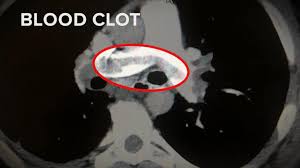

blood clot

A Mysterious Blood-Clotting Complication is Killing Coronavirus Patients

Once thought a relatively straightforward respiratory virus, covid-19 is proving to be much more frightening

One doctor replied that one of his patients had a strange blood problem. Despite receiving anticoagulants, the patient was still developing clots in various parts of his body. A second said she’d seen something similar. And a third. Soon, every person on the text chat had reported the same thing.

“That’s when we knew we had a huge problem,” said Coopersmith, a critical-care surgeon. As he checked with his counterparts at other medical centers, he became increasingly alarmed: “It was in as many as 20, 30 or 40 percent of their patients.”

With no clear patterns in terms of age or chronic conditions, some scientists now hypothesize that at least some of these abnormalities may be explained by severe changes in patients’ blood.